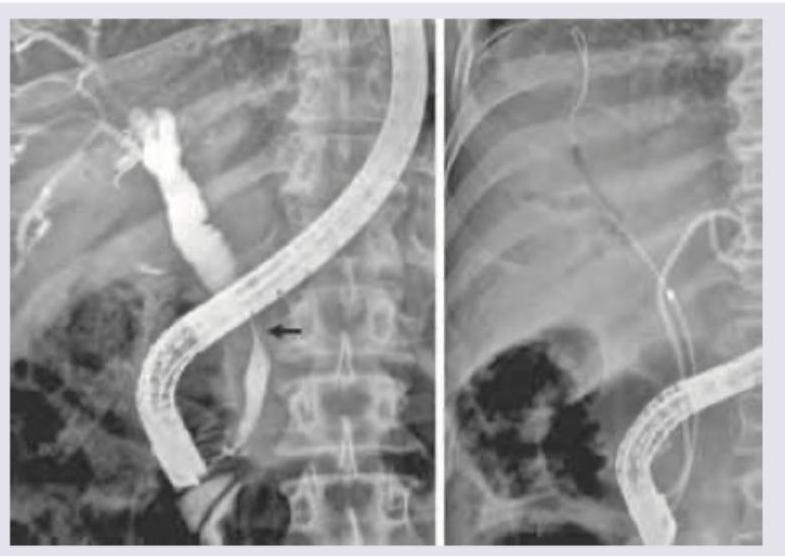

What type of choledochal cyst is shown in the image?

Explanation: ***Todani classification*** - The image provided shows an **ERCP (Endoscopic Retrograde Cholangiopancreatography)** with contrast in the biliary tree, demonstrating a dilated common bile duct (CBD) marked with an arrow. This appearance is characteristic of a **choledochal cyst**. - The **Todani classification** is a widely used system for categorizing choledochal cysts, which are congenital dilations of the biliary tree. *Bismuth classification* - The Bismuth classification is used to categorize **cholangiocarcinomas** (cancers of the bile ducts), particularly those affecting the hepatic confluence (Klatskin tumors). - It describes the extent of involvement of the hepatic duct bifurcation, which is distinct from the diffuse or localized dilations seen in choledochal cysts. *Johnson classification* - The Johnson classification is used for categorizing **duodenal ulcers**, specifically related to their location within the duodenum (e.g., gastric acid hypersecretion vs. normal acid production). - This classification is entirely unrelated to biliary tree pathologies. *Maastricht classification* - The Maastricht classification is used for grading **hepatic encephalopathy**, which is a neuropsychiatric complication of liver failure. - It describes the severity of neurological symptoms in patients with liver disease and has no relevance to imaging findings of biliary anomalies.

Explanation: ***2*** - The image displays a **diverticulum** protruding from the side of the **common bile duct (CBD)**, which is characteristic of a **Type II choledochal cyst**. - Type II choledochal cysts are rare, focal diverticula of the CBD, typically managed by excision. *1* - Type I choledochal cysts involve **fusiform or cystic dilation** of the extrahepatic bile duct, not a diverticulum protruding from the side. - They are the most common type and are usually treated with cyst excision and Roux-en-Y hepaticojejunostomy. *3* - Type III choledochal cysts, also known as **choledochoceles**, involve **dilation of the intraduodenal portion** of the CBD. - This typically appears as an intraduodenal cyst, which is not depicted in the image. *4* - Type IV choledochal cysts involve **multiple dilations** of the intrahepatic and/or extrahepatic bile ducts. - The image shows a single diverticular outpouching, not multiple dilations.